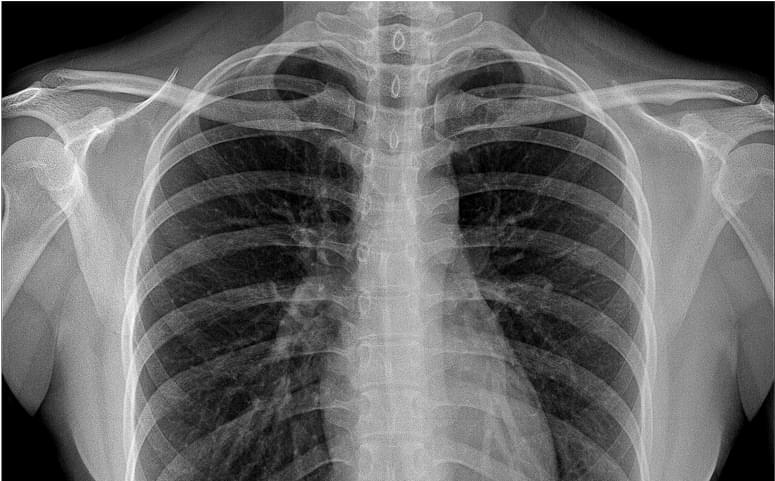

- 11% decrease in CXR reporting time in real world clinical practice.¹

Facilitate accurate diagnoses of complex and subtle cases with AI-decision support identifying up to 124 findings on CXR and 130 findings on CTB.

- Detect up to 15 critical and 36 urgent findings on chest X-ray.

- AI results are available within 20 seconds for CXR or 90 seconds for CTB.

Look beyond a single point solution. Unlock 100+ clinical findings with comprehensive AI solutions for CXR and head CT.

- Some of the world’s most comprehensive radiology AI solutions for CXR (124 findings) and CT Brain (130 findings).